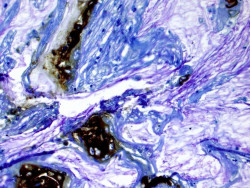

Encuentran un objetivo potencial para la esclerosis tuberosa

Investigadores de la Universidad de Cincinnati (Estados Unidos) han encontrado formas adicionales de centrarse en los procesos moleculares involucrados en la activación de cierto complejo de proteínas para desarrollar potencialmente nuevas terapias para un trastorno que causa tumores, según publican en la revista `Nature Metabolism`.